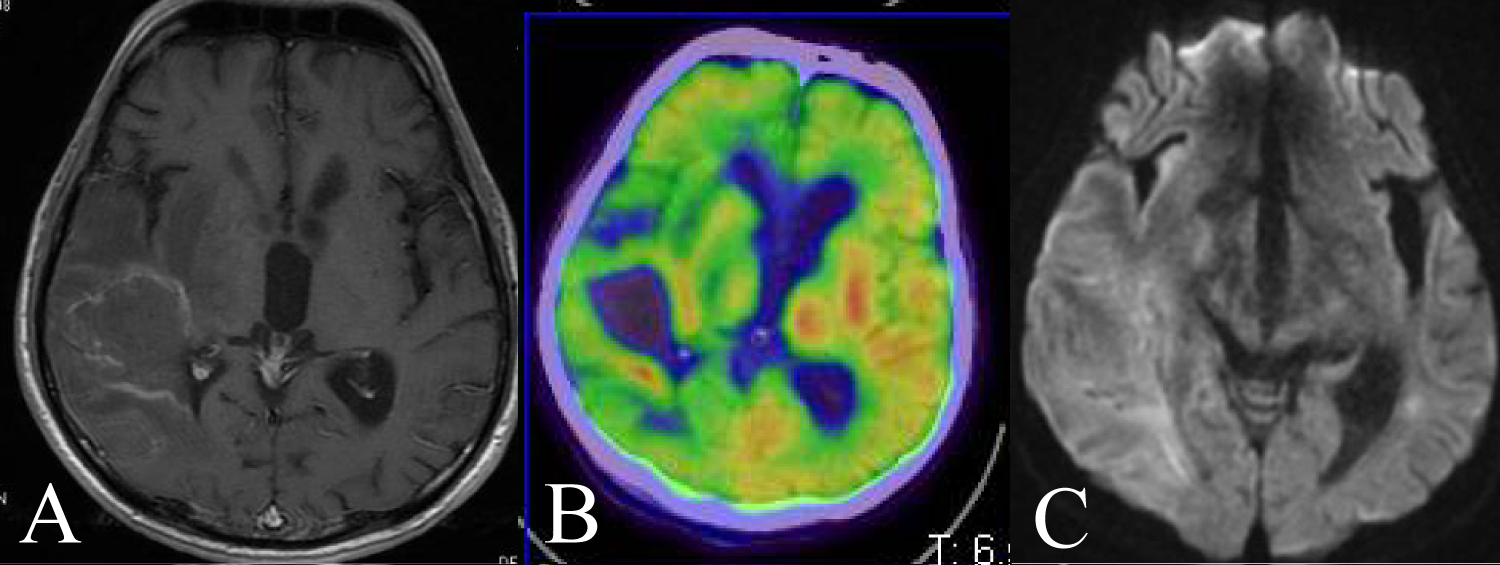

Case 6

28-year-old man presented dullness and we diagnosed his AIDS. His head MRI showed a ring enhancement at right caudate head (Figure 6A). FDG-PET showed ring like uptake and central low uptake at same lesion (Figure 6B). Histopathological findings were DLBCL. His CD4 positive T cell in number improved by combined ART, we performed rituximab plus high dose methotrexate therapy for him (Figure 6C). He survives at 84 months .

Figure 6: A 28 year-old man presented dullness. A) His head MRI showed a ring enhancement at right caudate head; B) FDG-PET showed ring like uptake and central low uptake at same lesion; C) DWI showed no clear findings. View Figure 6